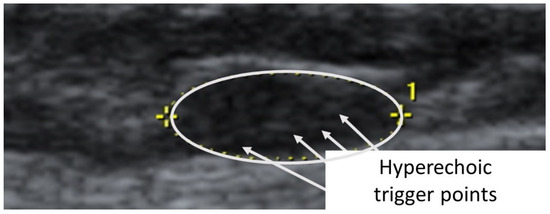

The second case was a 5′6”, 130 lbs., 26-year-old female subject (previously evaluated by both primary care physician and doctor of physical therapy to rule out other causes of symptoms other than TrPs) with left temporal headaches previously successfully treated by TrP-DN of the left upper trapezius. A taut band with palpable nodule within the left upper trapezius muscle was identified. As had been the case with previous headaches, the subject reported, upon palpation, pain referral symptoms spreading up the neck, around the ear, and into the temple [32]. The nodule was subsequently imaged in long-axis with a General Electric Voluson i Ultrasound System with a 12L-SC 13 MHz linear probe. A large hypoechoic contracture knot (61 mm × 22 mm) was identified (Figure 5) with smaller hyperechoic “speckles” (Figure 6) within the hypoechoic contracture knot (approximately 1 mm × 1 mm).

Figure 6.

Detailed ultrasound imaging assessment of the left upper trapezius muscle showing a collection of small hyperechoic (hypoperfused) “TrP speckles” within the contracture knot.

Considering that the pathogenesis of TrPs consists of dysfunctional motor endplates and they are ischemic areas in nature, previous studies may have mislabeled contracture knots as TrPs [19]. In each case presented, a hypoechoic/hyperperfused area of approximately 1 cm × 1 cm was visualized in the vicinity of the palpable nodule, with small hyperechoic/nonpalpable speckles of approximately 1 mm × 1 mm within each. Consistent with the multiple loci hypothesis presented by Hong and Simons [25], we suggest that the relatively large hypoechoic structures visualized as the TrP area in both subjects examined represent hyperperfused contracture knots with smaller, not previously distinguished, ischemic and hyperechoic TrPs within each.